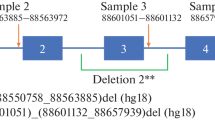

Mutation analysis of the P gene

Mutations of the P gene on chromosome 15q result in OCA2 (Gardner et al. 1992; Rinchik et al. 1993). The sequence of the P gene was determined in DNA from probands who were found to have no detectable mutations of the tyrosinase gene. In brief, the entire coding region and part of the flanking intron sequences for each of the 24 exons were individually amplified by using the polymerase chain reaction (PCR) with the primers listed in Table 1 (Saiki et al. 1988). The amplified product was directly sequenced by using the dideoxy method of Sanger with automated fluorescent DNA sequencing (LiCor). DNA from both parents was analyzed to confirm the origin of each mutation.